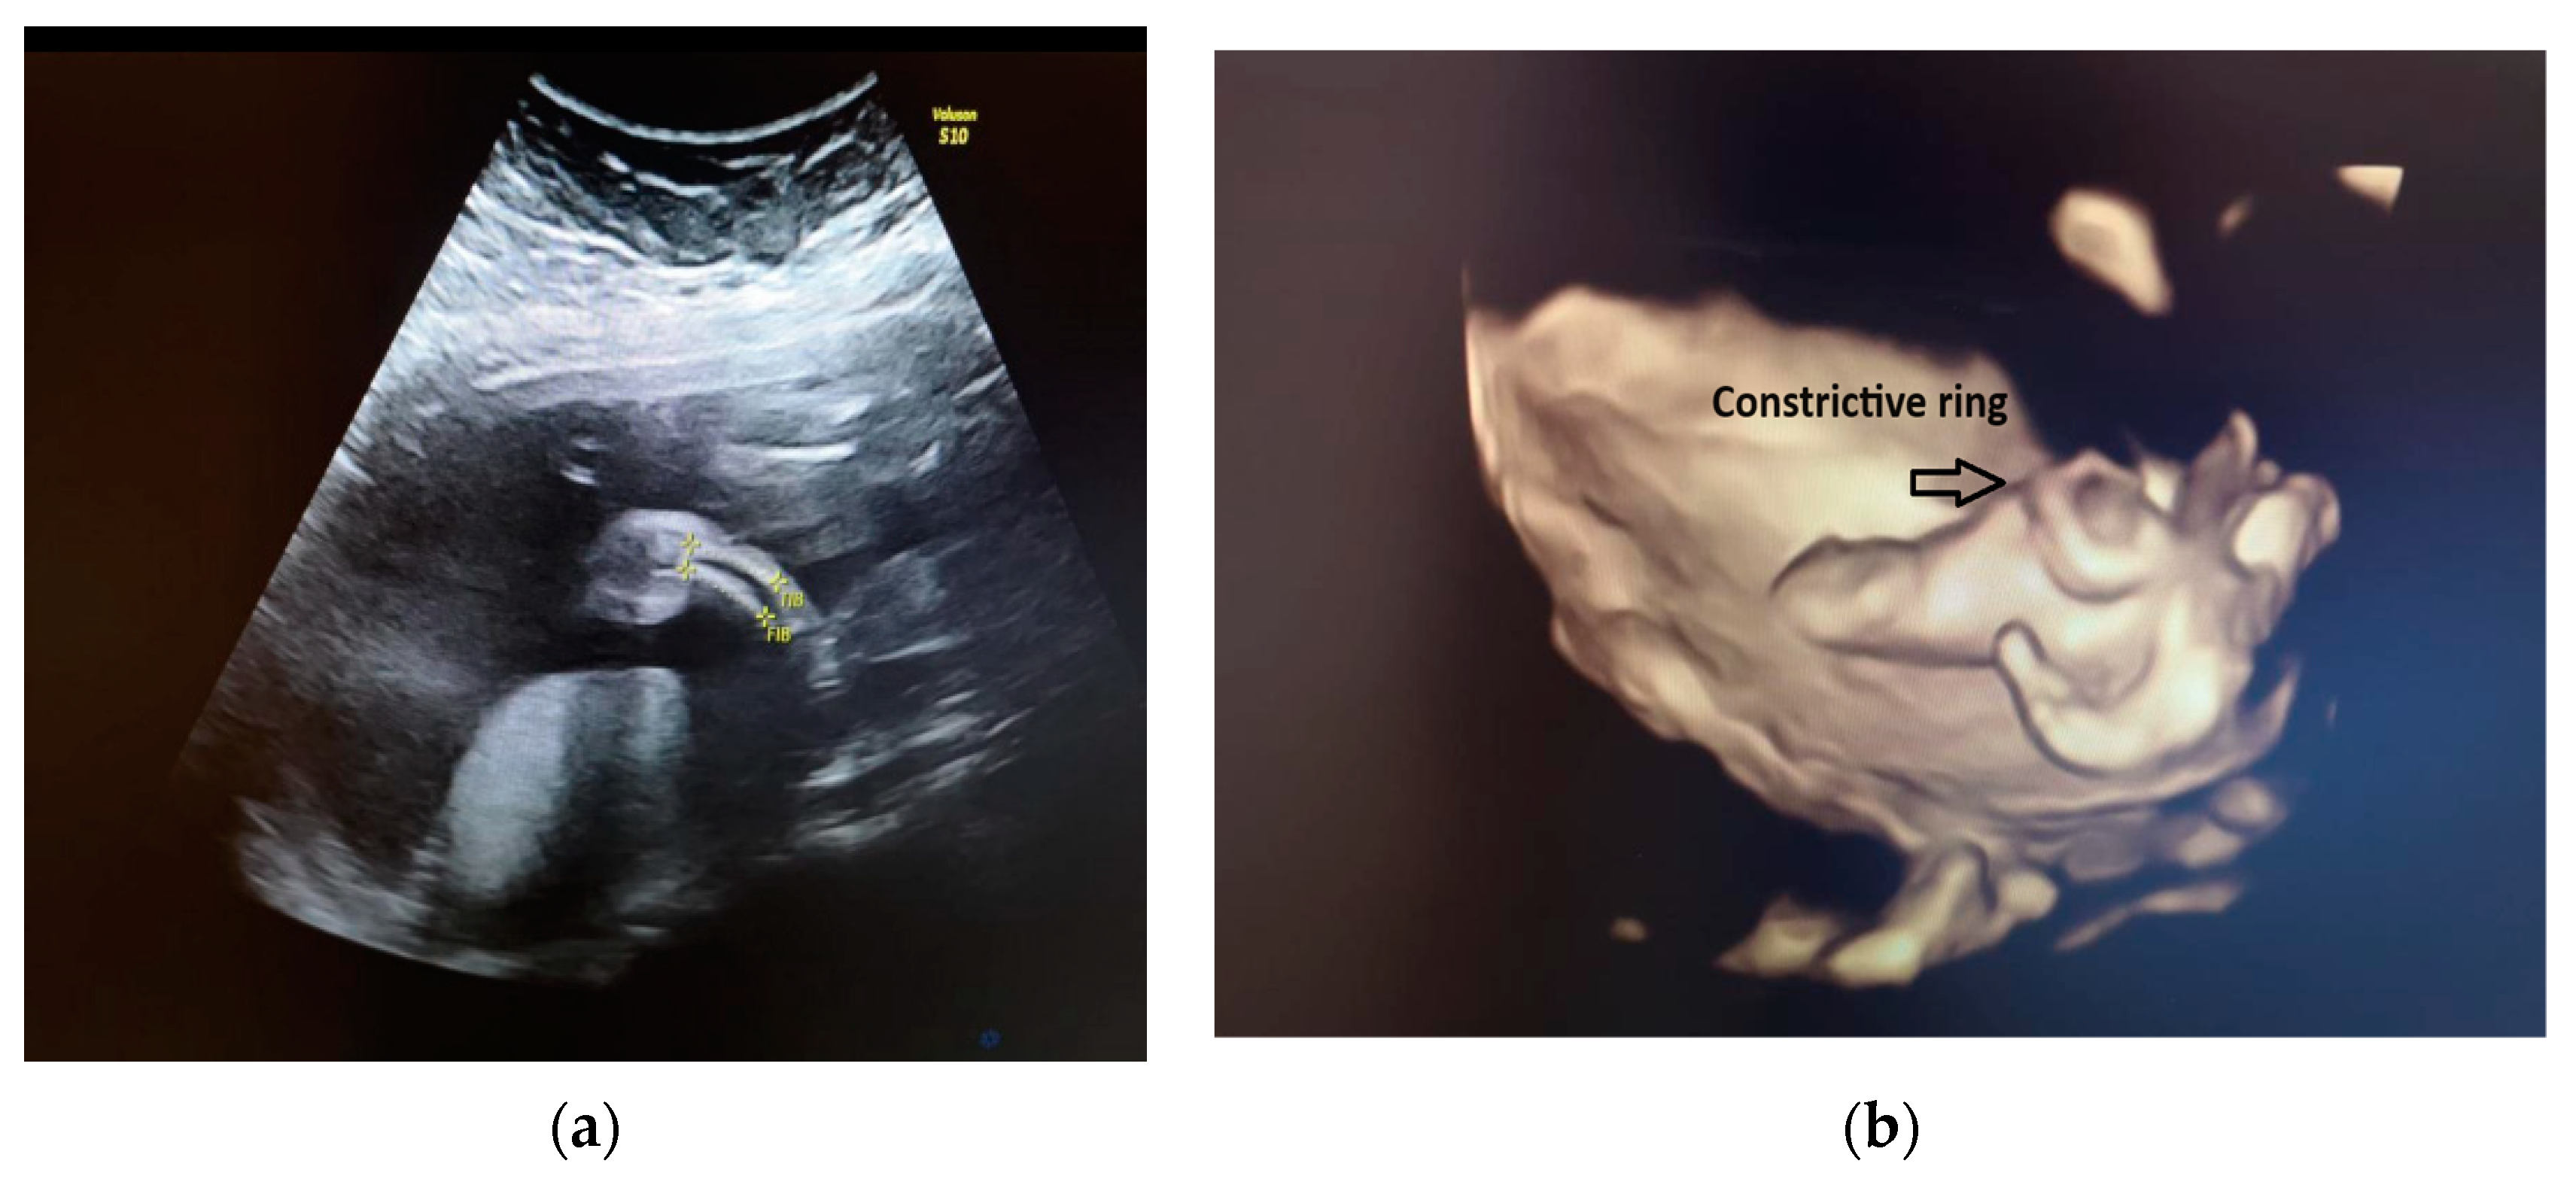

Our ultrasound examination revealed a normally grown female fetus, with an abnormal development of the right lower extremity. The right femur measured within normal ranges for the gestational age. There were flexion/extension movements at the level of the knee joint. Just below the right knee, the right leg appeared shorter and thinner than the contralateral one. The tibia and fibula from the right shin were below the third centile, with a mild curvature (see Figure 1a). Above the right knee, at the level of the right thigh, there was skin oedema. The right foot was shorter, and it had an abnormal shape (see Figure 1b). The rest of fetal anatomy appeared unremarkable, and in particular, the spine, ribs, upper extremities and left lower extremity had no additional changes.

Figure 1. (a) Fetal right leg; (b) 3D reconstruction of the fetal right leg.